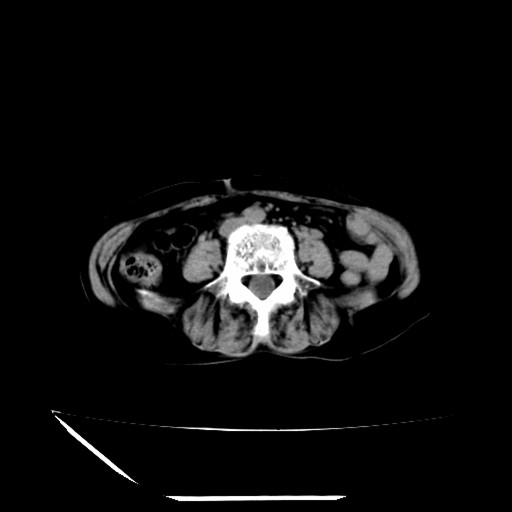

标题: CT16840:女-63岁,下腹部疼痛, [打印本页]

标题: CT16840:女-63岁,下腹部疼痛,

补充资料:血象是13.5,临床拟诊阑尾炎

本人诊断是右肾周围炎,阑尾炎,盆腔少许积液!

诊断右肾周围炎是因为我图像没有发完,诊断阑尾炎是因为相当于阑尾区连续两个层面可以看到增粗的阑尾显影。

支持阑尾炎!局部腹膜增厚,脂肪密度增高。应该手术治疗。